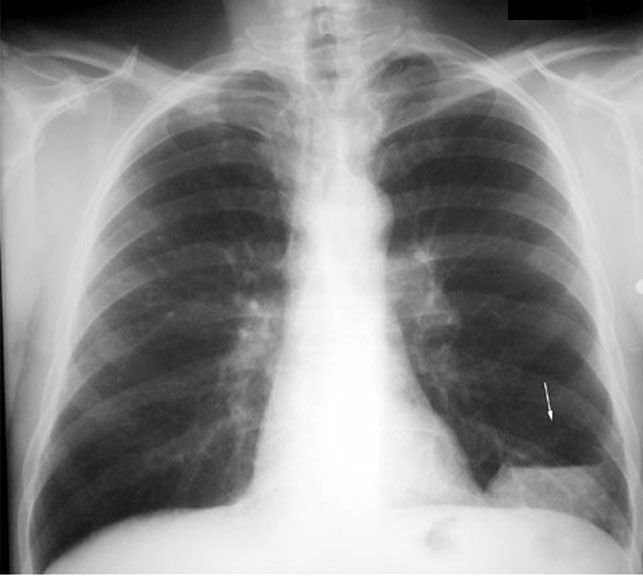

Bleb

• Avascular zone in LLL

• Thin wall of bleb

• Filled with serous fluid (bottom x-rays)

• No inflammatory changes

• Resolved spontaneously